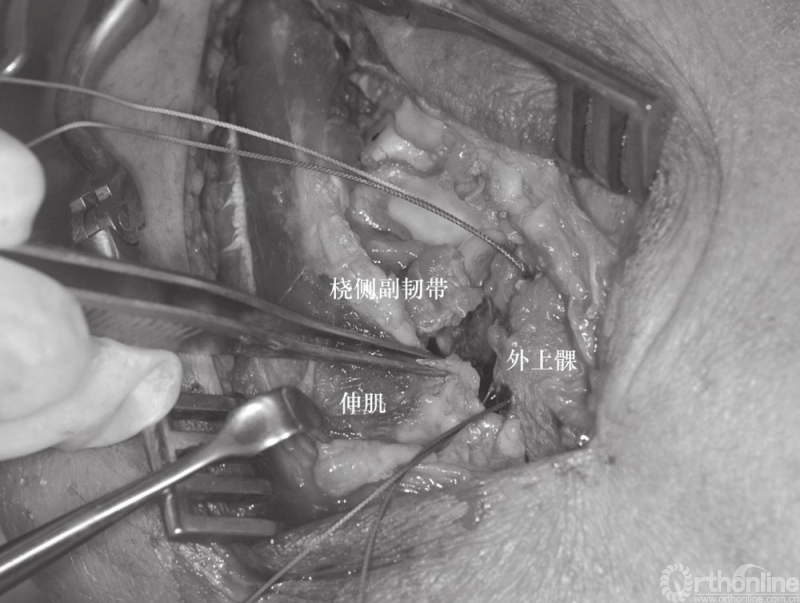

(2) 患者采用全麻、侧卧位,入路采用外侧入路,该入路便于切开复位、暴露肘关节、桡骨头重建和置换、固定冠状突以及后外侧韧带复合体的修复。外侧皮肤切口以肱骨外上髁为中心。前臂保持旋前位以增大骨间后神经与手术区域的距离。与单纯的桡骨头骨折采用的经肘肌和尺侧腕伸肌间的Kocher's间隔入路不同,对“恐怖三联征”患者可以利用损伤本身所造成的间隙进行暴露,而不需要特意的切开关节囊。损伤本身会导致关节囊、桡侧副韧带及大部分外侧肌肉软组织的破坏(图3)。

如果冠状突骨折块足够大,从外侧入路可以直接观察到,尤其是通过桡骨头的缺损处或者在桡骨头切除后。因此,在复位桡骨头之前先处理冠状突骨折,冠状突骨折块可以通过牙科刮匙进行复位和维持,然后经皮从尺骨背侧面置入空心螺钉进行固定。如果外侧入路进行固定存在困难,可以考虑直接由内侧入路进行暴露。小的游离骨折块可以去除(图4),套锁缝合前关节囊至尺骨可以加大稳定性(图5)。

图4 该损伤出现关节囊、桡侧副韧带及外侧肌肉软组织损伤(⋆桡骨头切除后)